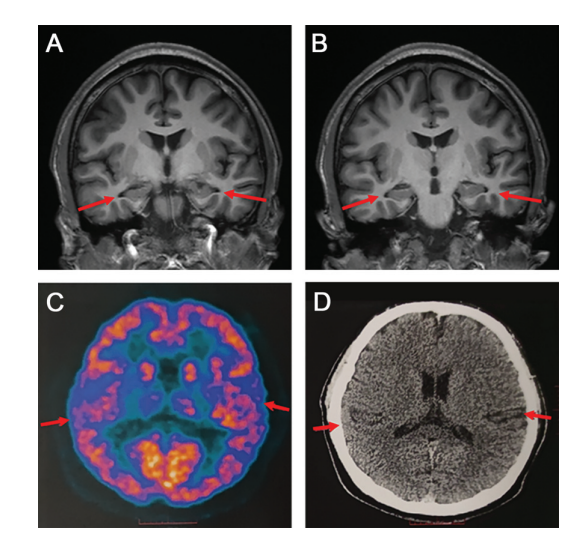

贾龙飞介绍,PET扫描和脑脊液指标检查,以及多种量表检测可以相辅相成,互相印证,以此才可以做出准确的临床诊断。

图源:首都医科大学宣武医院

研究小组对此病例的诊断为“疑似AD”,原因是仍有部分评估结果不符合AD的国际公认诊断标准(NIA-AA)。此外,该文章也提出了此项研究的局限性,由于患者比较年轻,不能接受大脑活检,需要长期随访进一步支持该团队的诊断。